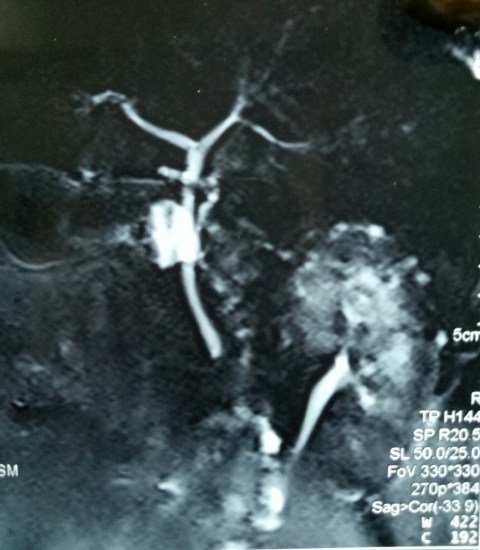

Another lap chole landing up in trouble. A young 30 years old male underwent a very difficult lap chole due to the frozen Calot’s triangle and a very thick walled gall bladder. Postoperatively had a bile leak which was 200 cc on the first postoperative day and then continued to decrease in amount gradually drying up in 18 days. MRCP shown below reported a small collection and a ? kink and narrowing at the site of cystic duct-CBD junction. Was it a cystic duct blow-out?